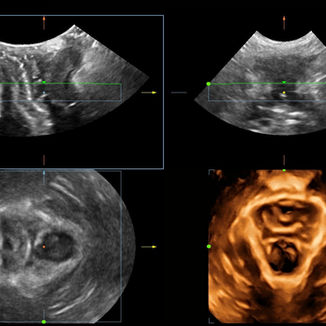

Realizing the increasing importance of ultrasound diagnosis on pelvic floor disorders, Smart Pelvic provides a new solution to greatly simplify the operation procedures, and to minimize the exam time for a standardized evaluation on pelvic floor. With extremely simple user-interaction, it generates a standard coordinate system and automatically provides related measurements within a few seconds.